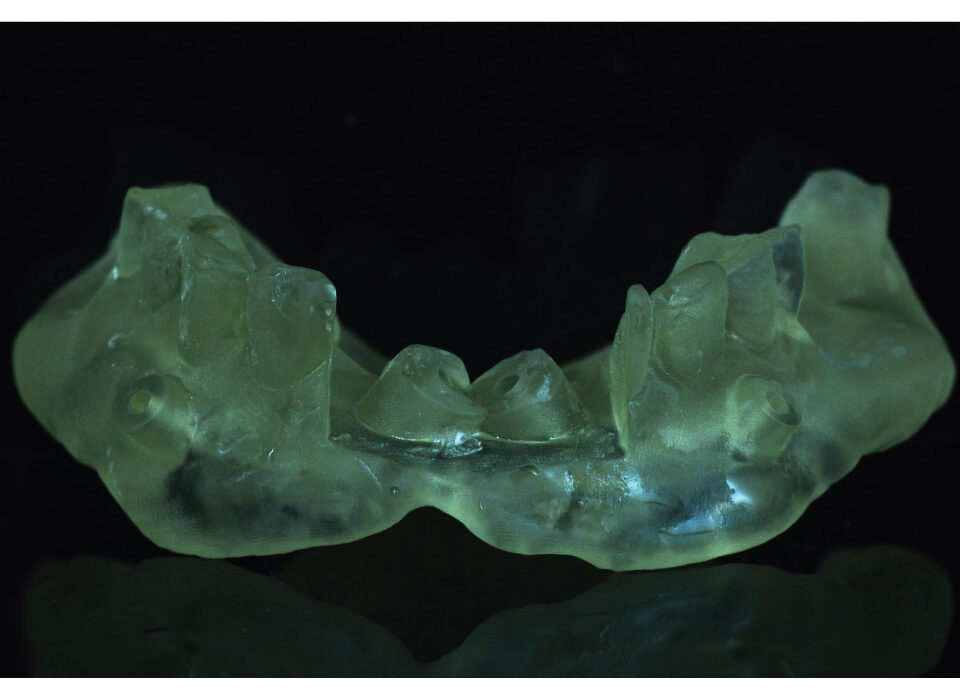

Surgical Guides

Surgical Guide is a digital tool that ensures accurate positioning and angulation of implants, which is crucial for the success and longevity of the implant. We fabricate different types of surgical guides, including tooth-borne, mucosa-borne, and bone-borne guides i.e stackable.